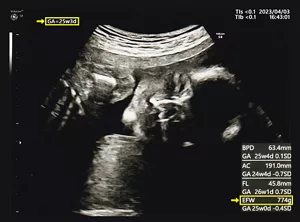

超音波写真では、「GA」(Gestational Age)もしくは「AGE」というのが妊娠週数、「EFW」(Estimated fetal weight)というのが推定体重のことです。

胎児発育曲線の横軸(妊娠週数)と縦軸(推定体重)が交わる位置に印をつけましょう。